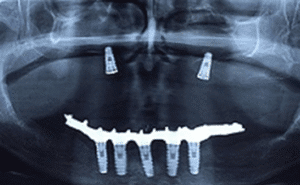

Reabilitação de maxilas atróficas com implantes zigomáticos: relato de caso clínico 02

Paciente de 48 anos, do sexo feminino, apresentando boa saúde geral, procurou atendimento odontológico para reabilitação maxilar. A mesma relatou